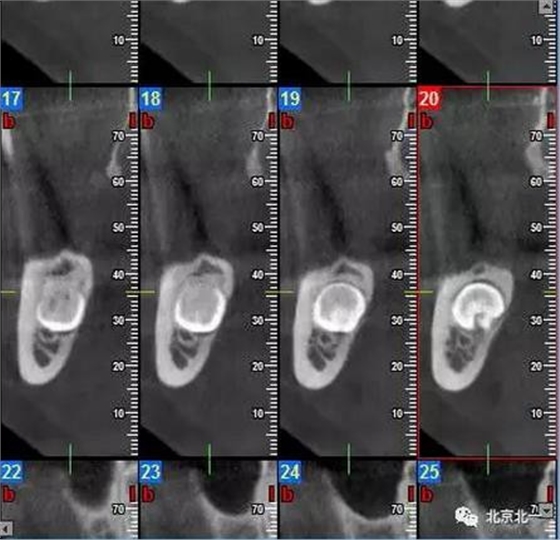

圖三:截面圖顯示神經管位置。